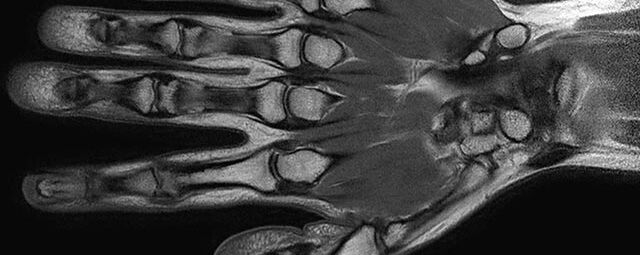

Gelenke

Hand

• Beurteilung von Knochen, Bändern und anderen Weichteilstrukturen der Gelenke nach Unfall.

• Arthrosediagnostik (Knorpelschaden)

• Impingement-Symptomatik

• Ursachenklärung bei wiederholter spontaner Gelenkluxation

• Ausbreitungsdiagnostik bei Gelenkentzündung, z.B. im Rahmen von rheumatischen Grunderkrankungen